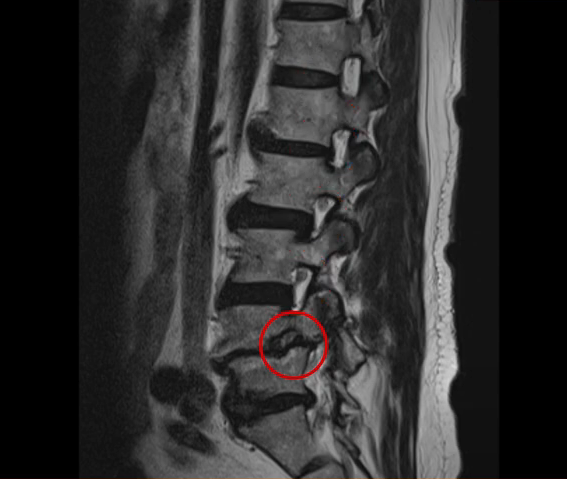

실제 저희 병원에서 추간공협착증 재활치료를 받은 환자분들의 두 가지 사례를 설명 드리겠습니다. 이분들은 심한 추간공 협착으로 인해 한쪽 다리의 심한 증상이 있었고 걷기 어려운 상태였습니다. 첫 번째 환자분은 69세로 전방전위증으로 인한 추간공협착증이 아주 심하게 발생한 분입니다. 여기 MRI를 보시면 심한 협착으로 인해 신경근이 눌려서 한쪽 다리에 마비가 오고 거의 걷지 못하는 상태가 되어 대학병원에서 유합술을 권유 받으셨습니다.

두 번째 환자분은 83세로 이 분도 마찬가지로 MRI를 보시면 전방전위증을 동반한 추간공협착증으로 한쪽 다리를 뗄 수가 없어서 걸음을 걷기가 어려워 동네 정형외과를 갔지만 동네 병원에서는 치료가 불가능하니까 큰 병원으로 빨리 가서 치료를 받으라는 권유를 받으셨습니다.